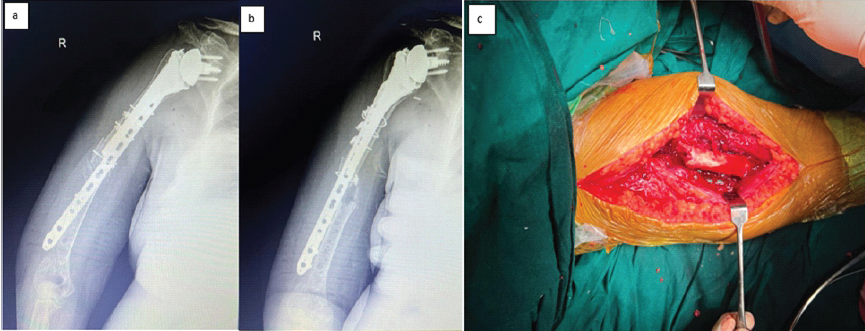

Figure 2: Anteroposterior and lateral radiographs showing well-fixed periprosthetic fracture utilizing 4.5 mm locking compression plates and cable system with cortico-cancellous bone graft interposed at fracture site (a and b). Clinical image taken during surgery showing periprosthetic fracture fixation with isolated intact radial nerve via posterior approach (c).